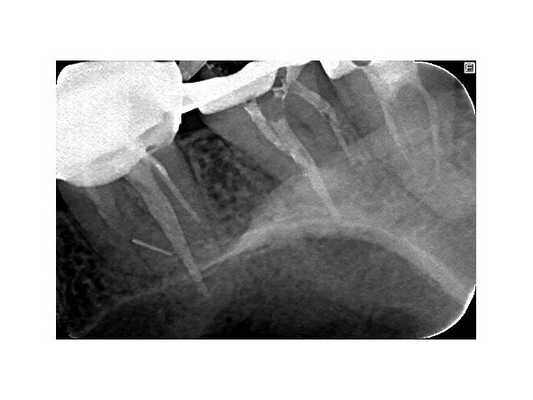

Третье посещение. Свищ отсутствует, перкуссия безболезненна. Проведена антисептическая обработка каналов, латеральная конденсация гуттаперчи + AH-plus ( методика пломбирования корневых каналов) .

Рекомендовано посещение врача-ортопеда для изготовления временной ортопедической конструкции на 17 зуб. Контрольный осмотр и КЛКТ назначены на сентябрь 2019 года.

После протезирования временной коронкой пациентка не предъявляла жалоб. На контрольной томограмме в сентябре 2019 года наблюдается уменьшение очага деструкции, восстановление дна гайморовой пазухи. Рекомендовано обратиться к врачу-ортопеду для протезирования постоянной ортопедической конструкцией. Осмотр в марте 2020 года.